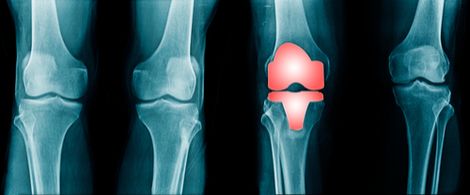

Knee replacement implants are used to resurface damaged areas of the knee joint to help alleviate pain and improve mobility. For most people, knee replacements work as intended, allowing them to walk, run, play sports, and dance without knee pain.

Unfortunately, defective knee replacements can have quite the opposite effect, potentially causing excruciating pain and other complications. There are many ways in which a knee replacement implant may be defective. Some possible ways include: